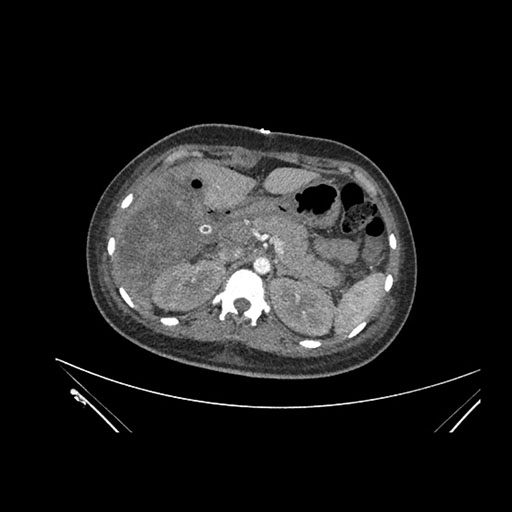

Imaging Analysis

Look through the patient's CT scan to identify any areas of concern for the necessary procedure.

Axial Arterial